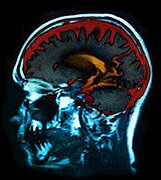

La enfermedad de Alzheimer parece desarrollarse de forma distinta en los cerebros de los pacientes negros, respecto a los blancos. Y los negros parecen ser más propensos a sufrir de distintos tipos de cambios cerebrales que también contribuyen a la demencia, informa un nuevo estudio.

La demencia de la enfermedad de Alzheimer por lo general se asocia con la acumulación de unas sustancias conocidas como placas y nudos en el cerebro. Pero hay otros cambios cerebrales que también pueden contribuir a la demencia, anotaron los autores del estudio.

Por ejemplo, los cerebros de las personas con demencia a veces contienen necrosis, que son minúsculas áreas de tejido muerto provocadas por mini accidentes cerebrovasculares (ACV), explicaron los investigadores. También pueden contener cuerpos de Lewy, otra forma de acumulación anómala de proteína en el cerebro que por lo general se asocia con la enfermedad de Parkinson.

Las autopsias de pacientes negros y blancos de Alzheimer revelaron que los negros eran más propensos que los blancos a experimentar cambios mixtos relacionados con la demencia, en contraste con el daño usualmente asociado con la demencia "pura" del Alzheimer, según el estudio.

El estudio encontró que de 81 pacientes blancos que murieron, el 42 por ciento solo mostraban las señales de la enfermedad de Alzheimer típica. Alrededor del 51 por ciento presentaban una mezcla de cambios cerebrales que incluían necrosis y cuerpos de Lewy, apuntaron los investigadores.

Pero entre los 41 pacientes negros que fallecieron, alrededor del 20 por ciento solo mostraban las placas y nudos usuales del Alzheimer. Casi todos los demás (más del 70 por ciento) experimentaron necrosis y cuerpos de Lewy además de los cambios cerebrales usuales del Alzheimer.

Los negros también tenían enfermedad de los vasos sanguíneos del cerebro más frecuente y grave, por ejemplo endurecimiento de las arterias, encontraron los investigadores.